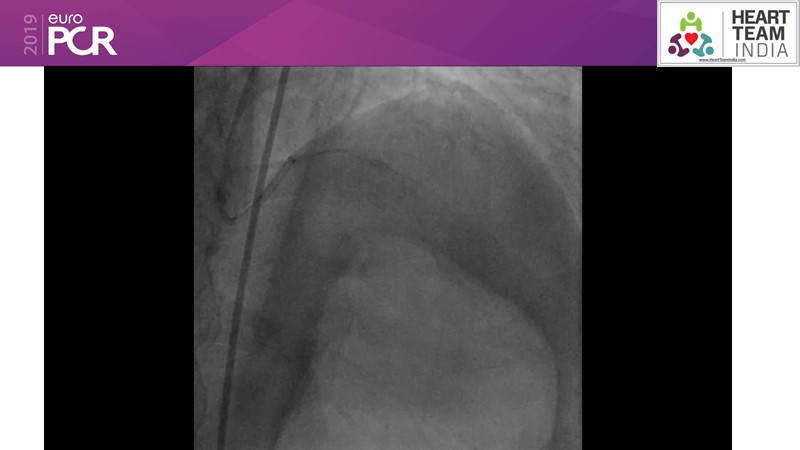

Ability to treat diabetic patients: DES + DCB strategy

Consult this session to get insights about the need for a dedicated drug eluting stent (DES), as well as the benefits of a DES+DCB strategy, for diabetes mellitus (DM) and acute MI (AMI) patients.